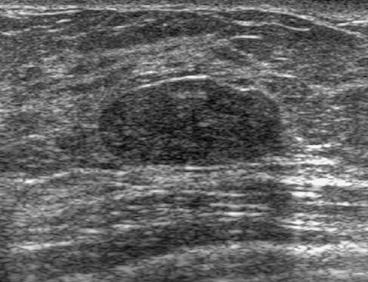

The target dataset was developed from 35 breast ultrasound scans that were segmented by an image-processing expert with extensive experience in breast lesion segmentation (the second author). The images, collected from the Web, are of different dimensions, ranging from to pixels (Figure 3, images resized for sake of illustration). These are the same images used to introduce EFIS originally [1].

Ultrasound images are generally difficult to segment, primarily due to the presence of speckle noise and low level of local contrast. It should be noted that the segmentation of ultrasound actually does require a complete processing chain, (including proper preprocessing and post-processing steps). However, the purpose of using these images was solely to demonstrate that the accuracy of the segmentation can be increased with the application of SC-EFIS.